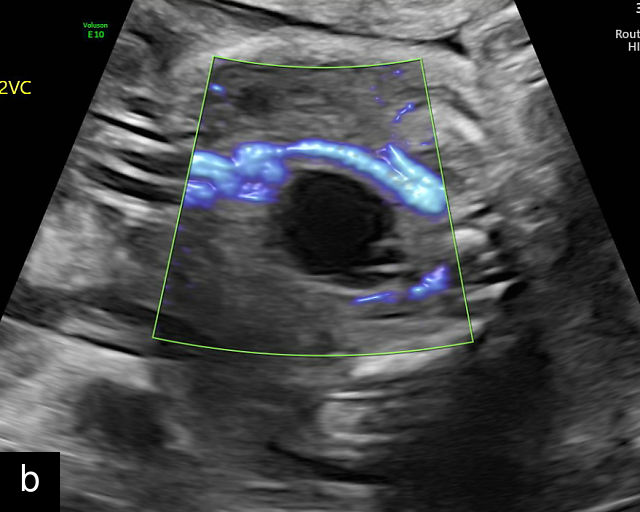

Vasa previa

Vasa previa refers to unprotected fetal vessels running through the membranes over the cervix.30,50,252,253 These vessels often rupture when the membranes rupture during labor or in late pregnancy, resulting in fetal hemorrhage and often exsanguination.252 As a result, this condition is associated with high perinatal mortality.35,252 A large study found a 56% perinatal mortality when vasa previa was not diagnosed prenatally.35 Prenatal diagnosis with ultrasound and cesarean delivery before labor or rupture of the membranes prevents this high perinatal mortality.254,255,256 Risk factors for vasa previa include second-trimester placenta previa or low-lying placenta, velamentous cord insertion, pregnancy resulting from in-vitro fertilization, multifetal gestation and placenta with accessory lobe.30,36,50,257,258,259,260,261

There are three types of vasa previa.30,262 In Type 1, the cord inserts into the membranes rather than the placenta. Unprotected vessels then traverse the membranes over the cervix to insert into the placenta (Figure 21a; Video 12). In Type 2, unprotected vessels running through the membranes over the cervix connect the main placental lobe with an accessory lobe (Figure 21b).263 In Type 3, there is generally a normal placental cord insertion, and unprotected vessels exit one placental edge, run through the membranes over the cervix and then boomerang to insert into the placental edge at another site (Figure 21c).25,28,29,264 Regardless of the type, all these expose the fetus to the same risks.